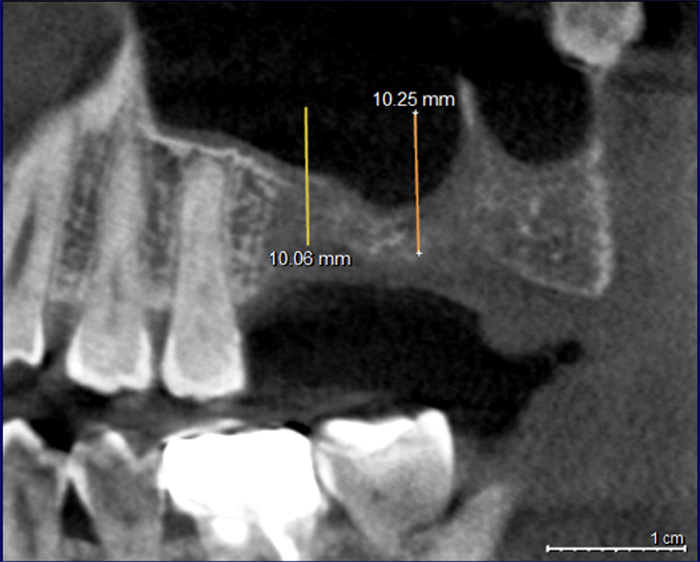

上顎骨3mm→13mmへ増やしたサイナスリフト(骨造成)症例